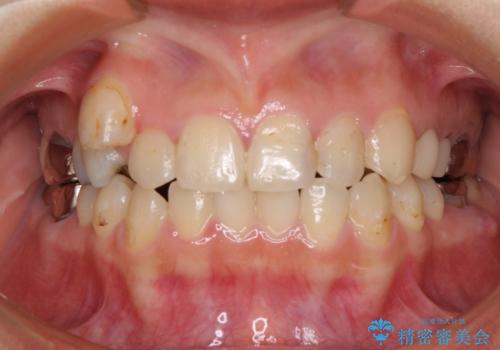

結婚式前にクリーニング希望の方

担当医 歯科衛生士